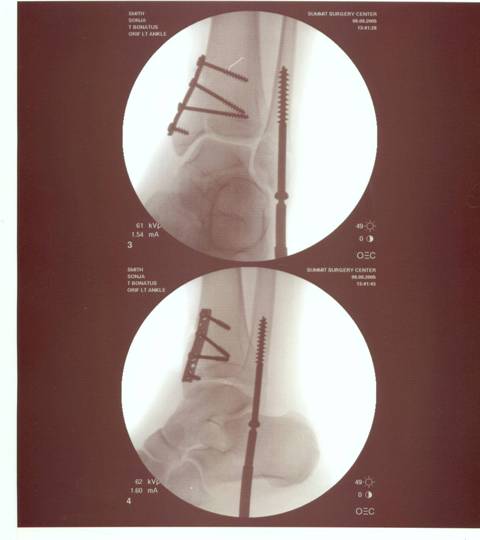

The X-Ray after surgery..